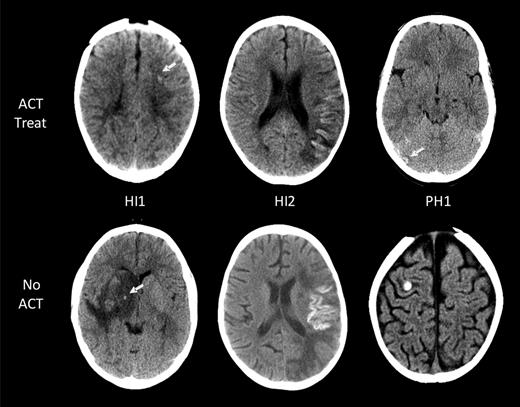

Eleven of the 14 children with ICH had images available for reanalysis and ECASS grading of ICH severity (Table 2).18 The ACT-associated ICH grades in the 7 asymptomatic patients were as follows: HI1 (no cortical laminar necrosis) in 3 patients, HI2 in 3, and PH2 in 1 (Figure 2). All 4 symptomatic ICH patients had HI1 (including cortical laminar necrosis) bleed severity. Among them, 1 patient had evidence of laminar necrosis only, 2 patients had evidence of both laminar necrosis and petechial hemorrhage, and the fourth patient had petechial hemorrhage.

ICH in children with AIS. Intracranial hemorrhages are classified according to the ECASS grading system. Representative examples of the 3 grades encountered (HI1, HI2, and PH1) are shown for both children on ACT (top row) and those not on ACT (bottom row). No larger hematomas or ECASS PH2 were observed in the ACT-treated group. White arrows point at areas of ICH.

Radiologic data included number and location of infarcts (vascular territory, brain structures, and laterality) and presence of ICH, including hemorrhagic conversion of infarcts at AIS diagnosis and during ACT. For every child with ACT-associated ICH, all brain imaging studies were re-evaluated by the study pediatric neuroradiologist (S.L.) and a pediatric neurologist (A.K. or G.d.V.) blinded to patient clinical data including ACT. ICH scoring was classified according to the European Cooperative Acute Stroke Study (ECASS) definitions: H0, no hemorrhage detected; HI1, hemorrhagic infarct 1: small petechiae, < 50% of infarct area (includes laminar necrosis); HI2, hemorrhagic infarct 2: confluent petechiae, > 50% of infarct area; PH1, parenchymal hemorrhage 1: blood ≤ 30% of infarct area, no or slight space effect; and PH2, parenchymal hemorrhage 2: blood ≥ 30% of infarct area, substantial space effect.18 Changes in ECASS scores over time were documented.